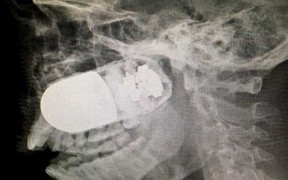

Những hình ảnh X-quang cho thấy quả lựu đạn chưa nổ cắm thẳng vào khuôn mặt một người lính ở Colombia sau tai nạn quân sự.